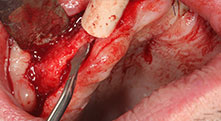

Could you describe briefly, for example, your procedure for mobilizing bone blocks for transplantation?

Bratu: We prefer to harvest bone from the external oblique ridge of the posterior mandible, not from the interforaminal region. After the soft-tissue incision, we use the new saws to define the amount of bone to harvest. With this approach, we also use them for the entire preparation in almost 80% of cases. We may also use other piezo instruments and then at the end a chisel to mobilize the block. We find that this is a very effective surgical technique.

Bratu: We like to use the sandwich technique for augmentation in the lateral mandible. A bone cover is prepared with the piezo saw and the crestal fragment is fixed with microscrews. We place a mixture of autologous bone and xenogenic bone replacement material in between. This works very reliably. You should always ensure sufficiently dimensioned vertical cuts when splitting the alveolar ridge in the mandible. Otherwise the bone may fracture easily.

Bratu: I consider piezo surgery a great leap forward in oral surgery. The technique makes bone preparation safer and easier. Little bone is lost, for example in extractions. This is very important in the aesthetic zone, particularly if immediate implantation is planned. Piezo surgery is also safer for soft tissue: injuries to membranes in the sinus are basically history, as are nerve injuries when bone blocks are being harvested. Data indicating reduced postoperative swelling and pain are also available. Piezo surgery is also ideal for preparation of sinus septa. And last but not least, our patients benefit from the atraumatic nature of this technology.